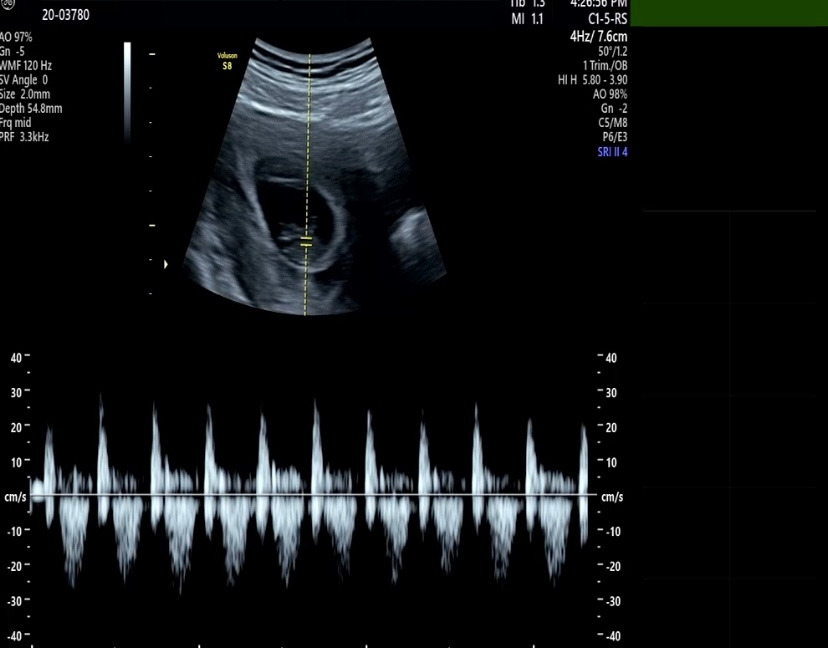

젤리곰을 봤다. 아직은 손가락 한마디 정도 되는 크기인데도, 사람 모습을 갖춰가는 게 너무 신기하다. 의사 선생님이 이제는 3~4주 뒤에 1차 기형아 검사를 할 때 보자고 하셨다. 1주일도 이렇게 긴데, 어떻게 그 시간을 기다릴지 벌써 걱정이다. 아내보고 건강한 산모라고 했다. 그래서 아기도 건강하게 잘 크고 있다고 한다. 만성 운동부족인 아내를 걱정하는 건 나뿐인가 보다. 그래도 전문가에게 그런 이야길 들으니 안심이 되고 힘이 난다.